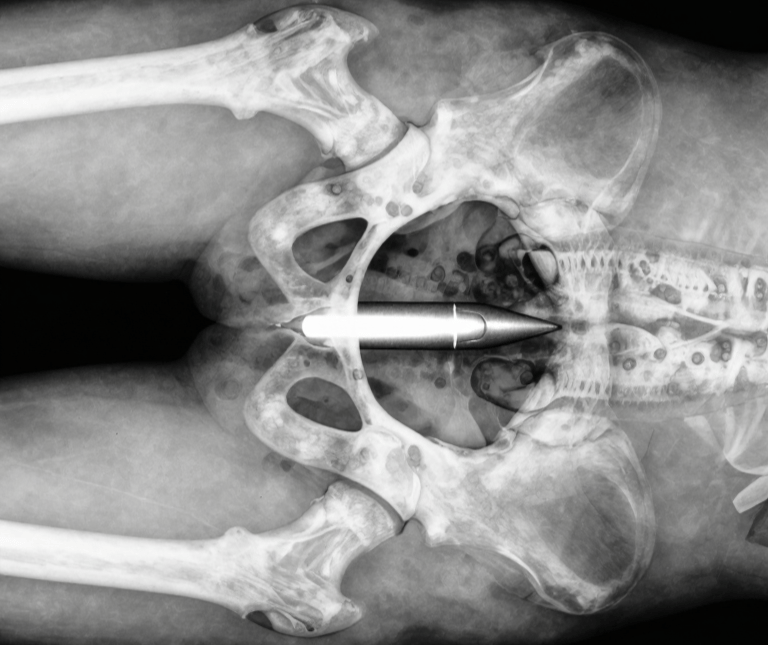

A Frenchman Showed Up to Hospital With a WWI Shell Buried In His Ass

Not a figure of speech. Not a metaphor. A 20-centimeter artillery shell from 1918 — lodged exactly where you're now picturing it. Upon identifying the shell by X-ray, Doctors called the building. The hospital was evacuated and a security perimeter went up around the operating theatre. The most shocking part? This is the third time someone in Europe has done this.